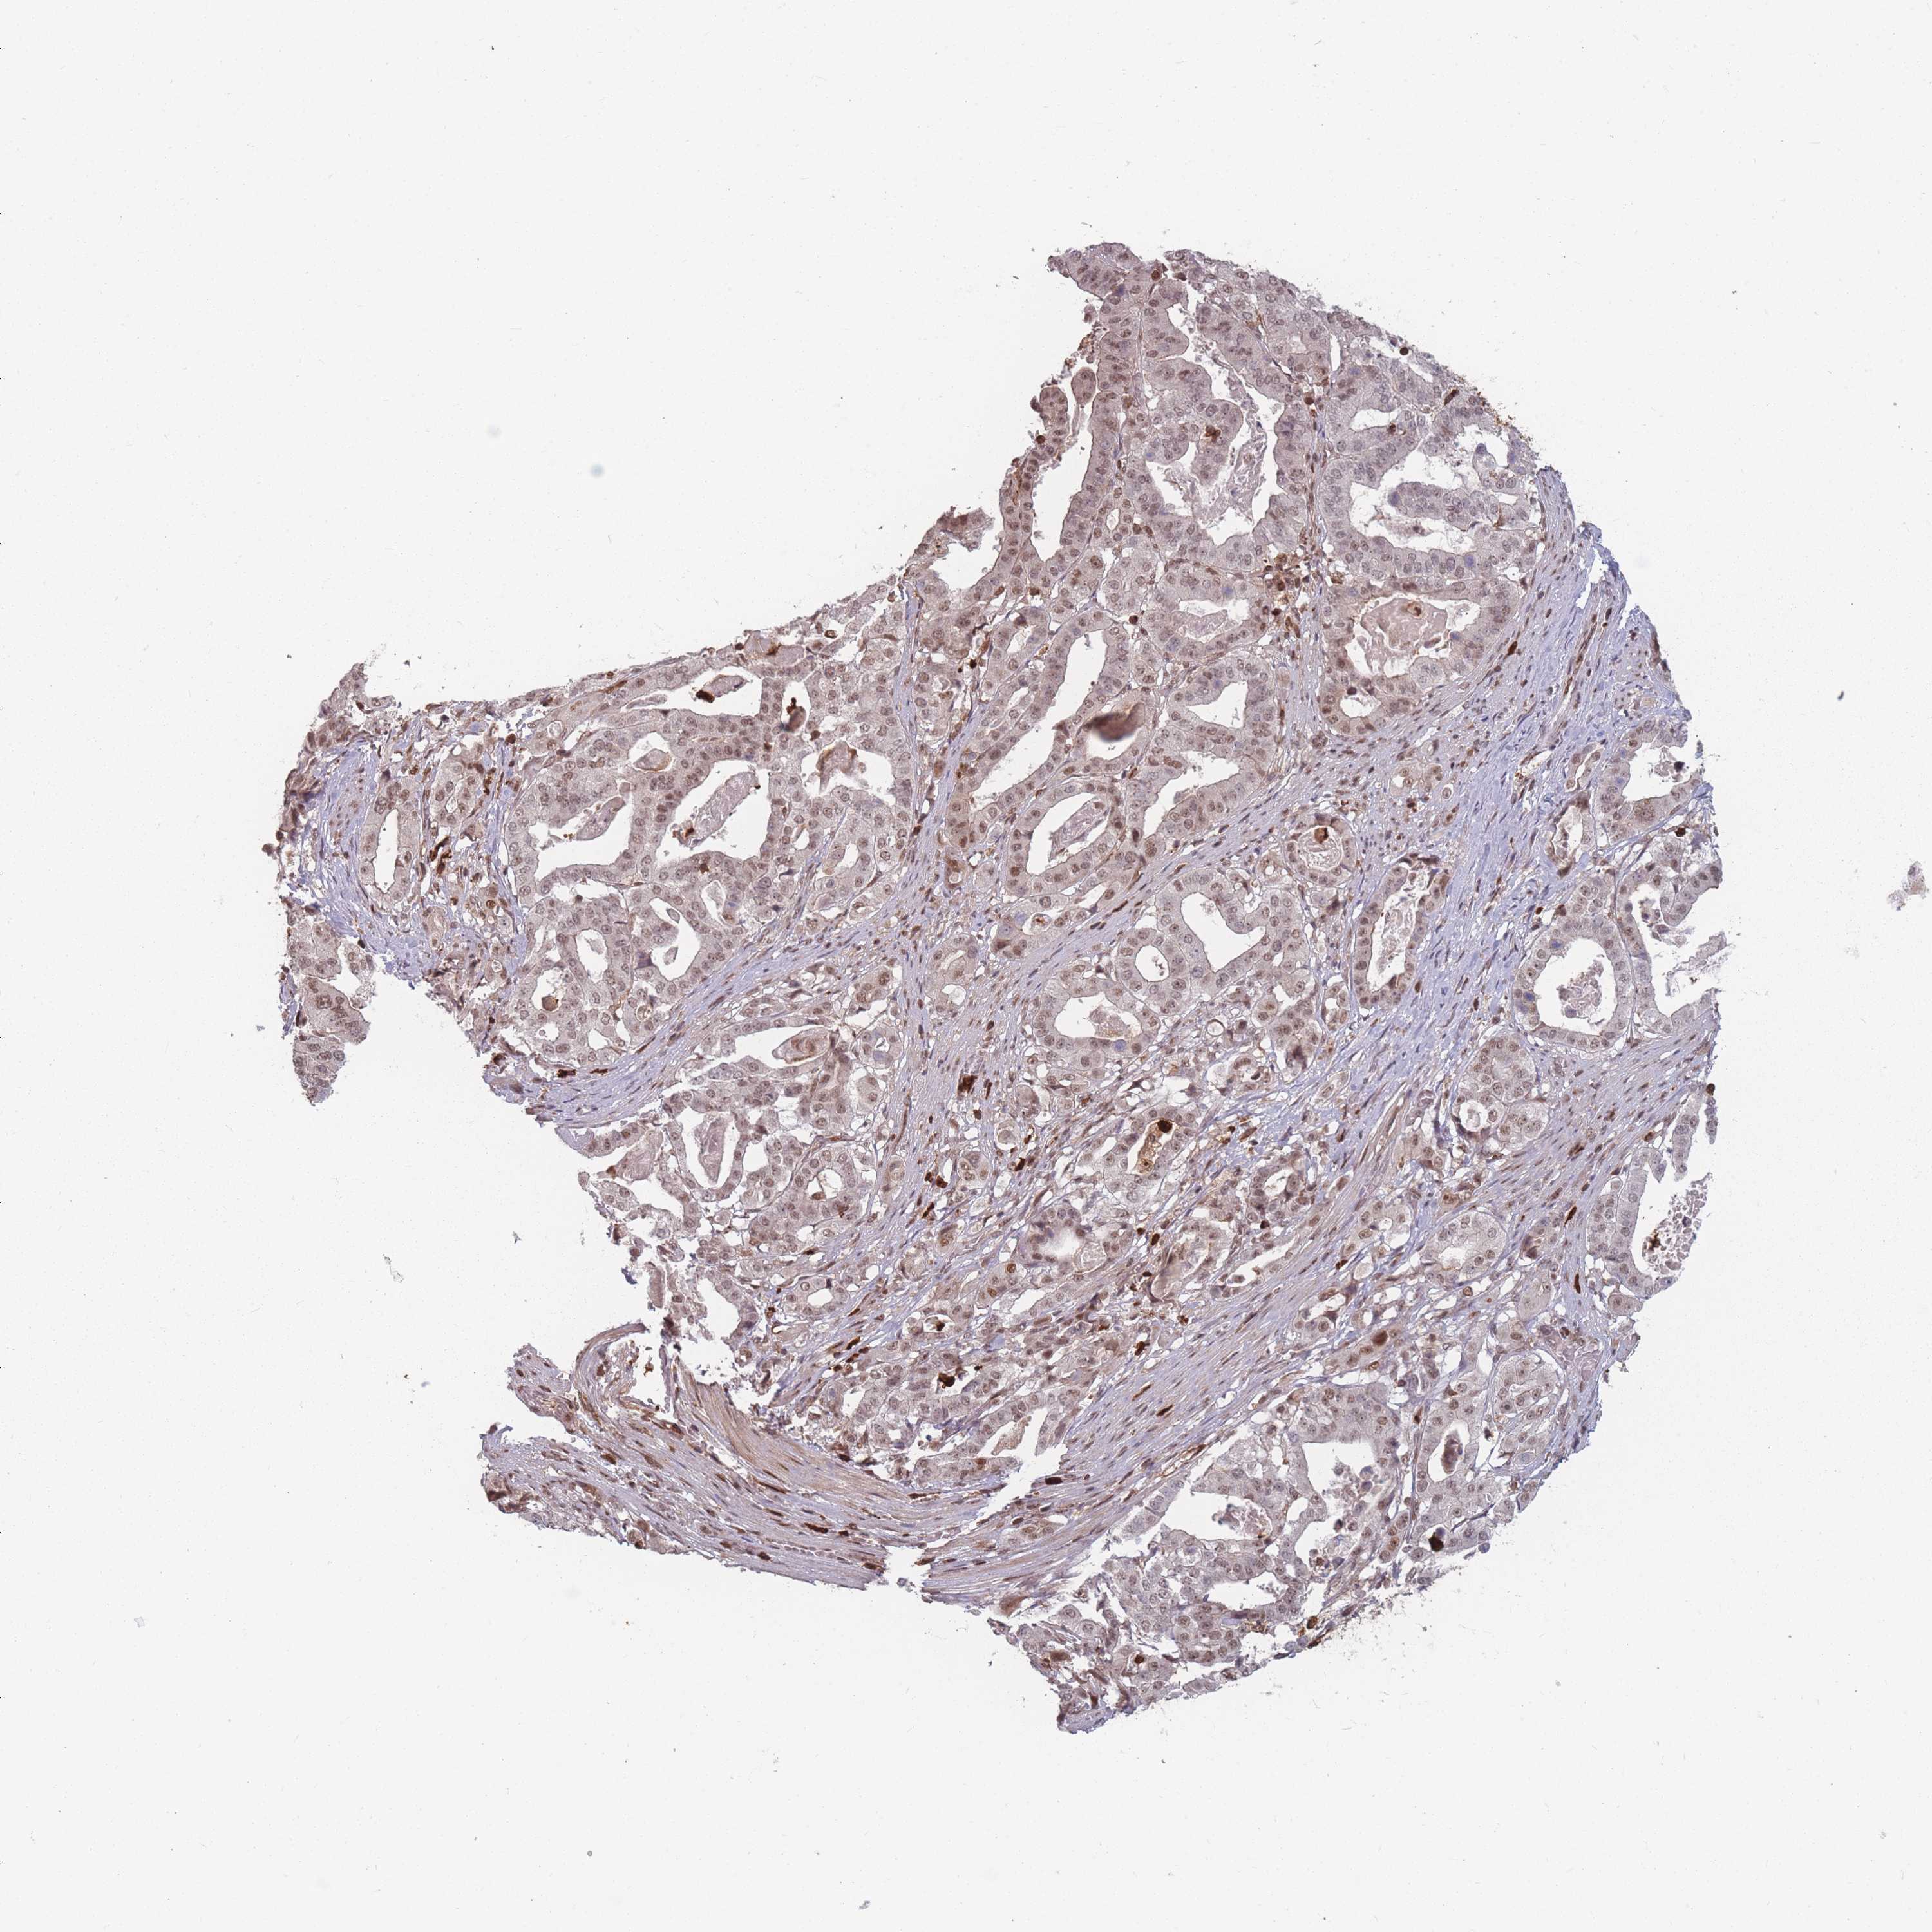

STOMACH CANCER - Protein expressioni

A mouse-over function shows sample information and annotation data. Click on an image to view it in a full screen mode. Samples can be filtered based on level of antibody staining by selecting one or several of the following categories: high, medium, low and not detected. The assay and annotation is described here.

Note that samples used for immunohistochemistry by the Human Protein Atlas do not correspond to samples in the TCGA dataset.

Antibody stainingi

Antibody staining in the annotated cell types in the current human tissue is reported as not detected, low, medium, or high, based on conventional immunohistochemistry profiling in selected tissues. This score is based on the combination of the staining intensity and fraction of stained cells.

Each image is clickable and will lead to virtual microscopy that enables deeper exploration of all samples and also displays staining intensity scores, fraction scores and subcellular localization as well as patient and tissue information for each sample.

Antibody HPA043470

Antibody HPA048143

Staining

High

Medium

Low

Not detected

Intensity

Strong

Moderate

Weak

Negative

Quantity

>75%

75%-25%

<25%

None

Location

Nuclear

Cytoplasmic/membranous

Cytoplasmic/membranous,nuclear

Adenocarcinoma, NOS